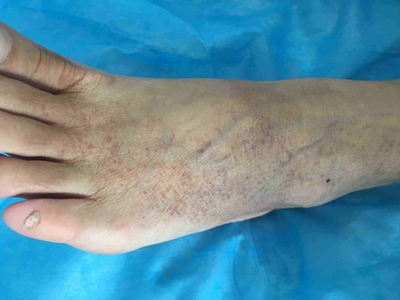

过敏性紫癜又称亨-许紫癜,是一种IgA型抗体介导的变态反应性毛细血管和细小血管炎,好发于儿童和青少年,90%为10岁以内,男性多于女性。本病皮损为红色丘疹和淤斑,好发于下肢,以小腿伸侧为主,重者可波及上肢、躯干,病程长短不一,易复发。

过敏性紫癜发病前常有上呼吸道感染,随后出现皮肤紫癜,多见于四肢,对称分布,伸侧较多,分批出现,初起呈紫红色斑丘疹,高出皮面,压之不褪色,数日后转为暗紫色,最终呈棕褐色而消退。少数重症患者紫癜可融合成大疱伴出血性坏死。部分患者可伴有荨麻疹和血管神经性水肿。皮肤紫癜一般在4-6周后消退,部分患者间隔数周或数月后又复发。若累及关节,可表现为关节肿胀、疼痛及功能障碍。累及肾脏时,可表现为血尿、蛋白尿,偶见水肿、高血压及肾衰竭等。